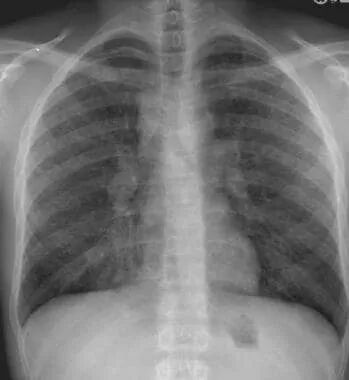

图1 双肺门淋巴结肿大

若无病理学依据,可以结合胸部影像学、支气管镜的相关检查结果,除外其他肉芽肿性疾病后,临床拟诊肺结节病,但需要密切临床随诊、动态观察病情变化。